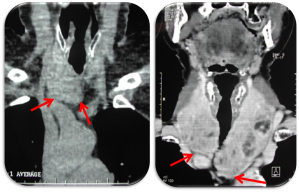

En fonction de la taille du goitre et en cas de suspicion clinique et échographique d’un caractère plongeant (pôle inférieur de la glande non palpable ou non visualisé en échographie), une imagerie par scanner du cou et du thorax permet de déterminer le caractère cervciothoracique du goitre et ses rapports anatomiques particulièrement vasculaires.